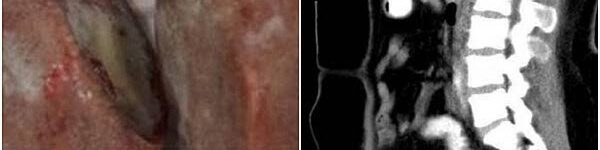

A formação das pedras na vagina se deu, segundo os registros, pelo acúmulo de urina em parte indevida: no caso relatado, o acúmulo se deu provavelmente pelo quadro de fístula ureterovaginal apresentado pela paciente, quando há uma abertura na comunicação entre a bexiga e a vagina, causando perda involuntária de urina. A mulher vivia com problemas na bexiga desde os 5 anos de idade, após um acidente de automóvel provocar uma ruptura no órgão, e o ferimento teria causado o quadro geral descoberto. -Pantone cria gráfico de cores de xixi para você saber se está hidratado o suficiente Além do local onde os cálculos vaginais foram encontradas, outro aspecto extraordinário do caso é o tamanho das formações: enquanto as mais comuns pedras nos rins ou na vesícula biliar medem entre 5 e 7 milímetros, as pedras vaginais da indonésia mediam 3,6 cm por 5 cm em um caso, e 5 cm por 5,8 cm em outro – eram, portanto, do tamanho aproximado de bolas de pingue-pongue, ocupando inteiramente uma palma de mão. Os exames de imagem revelaram uma pedra presa à parede da bexiga, e outra à parede do reto, e ambas foram retiradas em cirurgia.

O caso foi publicado na revista científica Urology Case Reports, e relatou que a jovem apresentava menstruação irregular e dolorosa por toda sua vida, mas jamais procurou tratamento ou orientação médica. “A obstrução vaginal também causará problemas de qualidade sexual e infertilidade em uma mulher adulta”, diz o texto. Segundo os médicos, o acidente de trânsito em sua infância pode ter ferido outros órgãos reprodutivos, e explicar o quadro da paciente, que não foi identificada